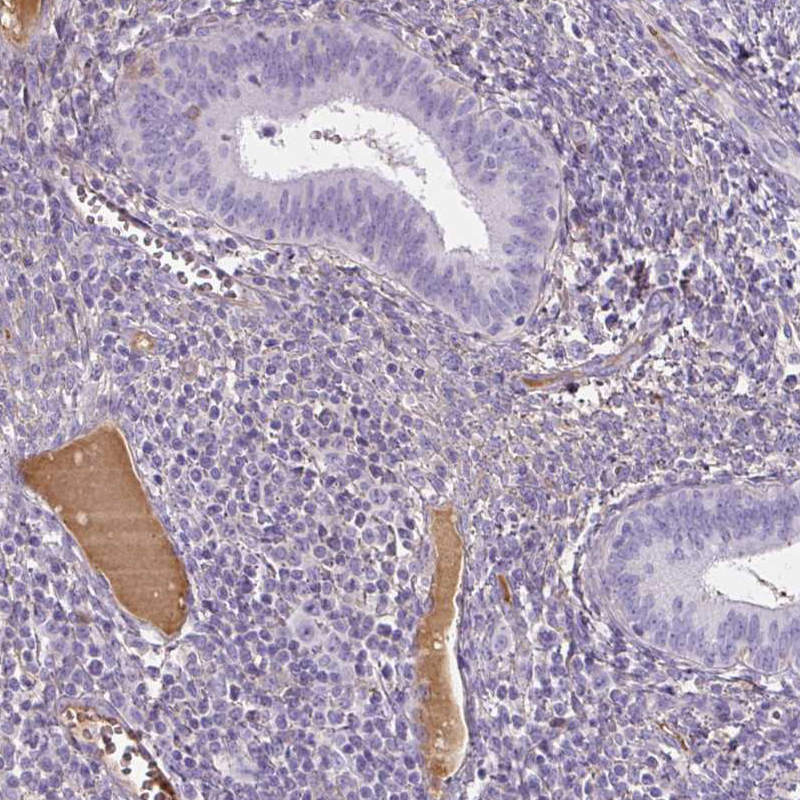

Immunohistochemical staining of human colon shows moderate positivity in plasma.